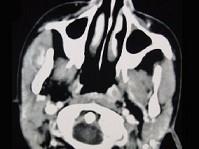

问题 16岁女性患者,右侧面颊部肿胀,CT扫描如图所示,应考虑为 ( )

选项 A、右侧咬肌区淋巴管瘤 B、右侧咬肌区慢性淋巴管炎 C、右侧咬肌区脂肪瘤 D、右侧咬肌区皮样囊肿 E、右侧咬肌区血管瘤

答案 E